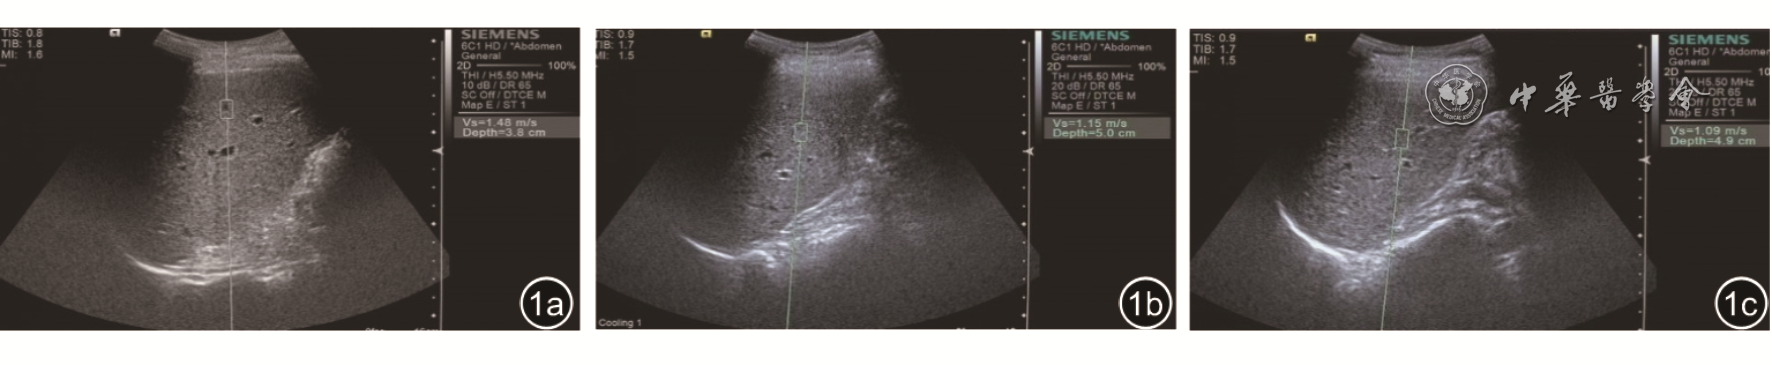

二、肝炎患者治疗前后VTQ值比较

表3 2组受试者治疗前后声触诊组织定量值比较(m/s, |

| 组别 | 例数 | 治疗前 | 治疗1个月 | 治疗3个月 | F值 | P值 |

|---|---|---|---|---|---|---|

| DILI组 | 34 | 1.74±0.18 | 1.14±0.23a | 1.06±0.40 a | 57.438 | 0.000 |

| VH组 | 40 | 1.70±0.41 | 1.59±0.16 | 1.12±0.23ab | 46.180 | 0.000 |

| t值 | 0.527 | 9.882 | 0.805 | |||

| P值 | 0.600 | <0.001 | 0.423 |

注:与治疗前比较,aP<0.05;与治疗后1个月比较,bP<0.05 |